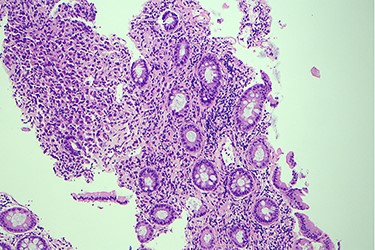

Surveillance colonoscopy in 2018 identified a fungating nonobstructing mass in the sigmoid colon (Fig. 1). Histology from a biopsy showed poorly differentiated carcinoma (Fig. 2). Given the history of breast cancer, further immunohistochemical staining was performed, which was positive for E-cadherin (Fig. 3), ER (Fig. 4), PR, GATA3 binding protein (GATA 3) (Fig. 5) and negative for Cytokeratin 20 (CK20) (Fig. 6). This confirmed metastatic invasive ductal carcinoma of breast. A positron emission tomography (PET) scan showed only the retroperitoneal mass involving the proximal sigmoid colon with no other evidence of metastatic disease (Fig. 7).

Histology slide showing positive immunohistochemical staining of estrogen receptor.

Histological examination often involves multiple markers to further assist in the diagnosis. According to the literature, helpful markers include GCDFP-15, ER, PR and GATA-3 [5, 9]. Expression of CK-7 and absence of CK-20 is also commonly seen in ductal carcinoma [10]. The immunohistochemical profile for our case was positive for E-cadherin, CK-7, ER, GATA-3 and negative for CK-20 and CDX2.